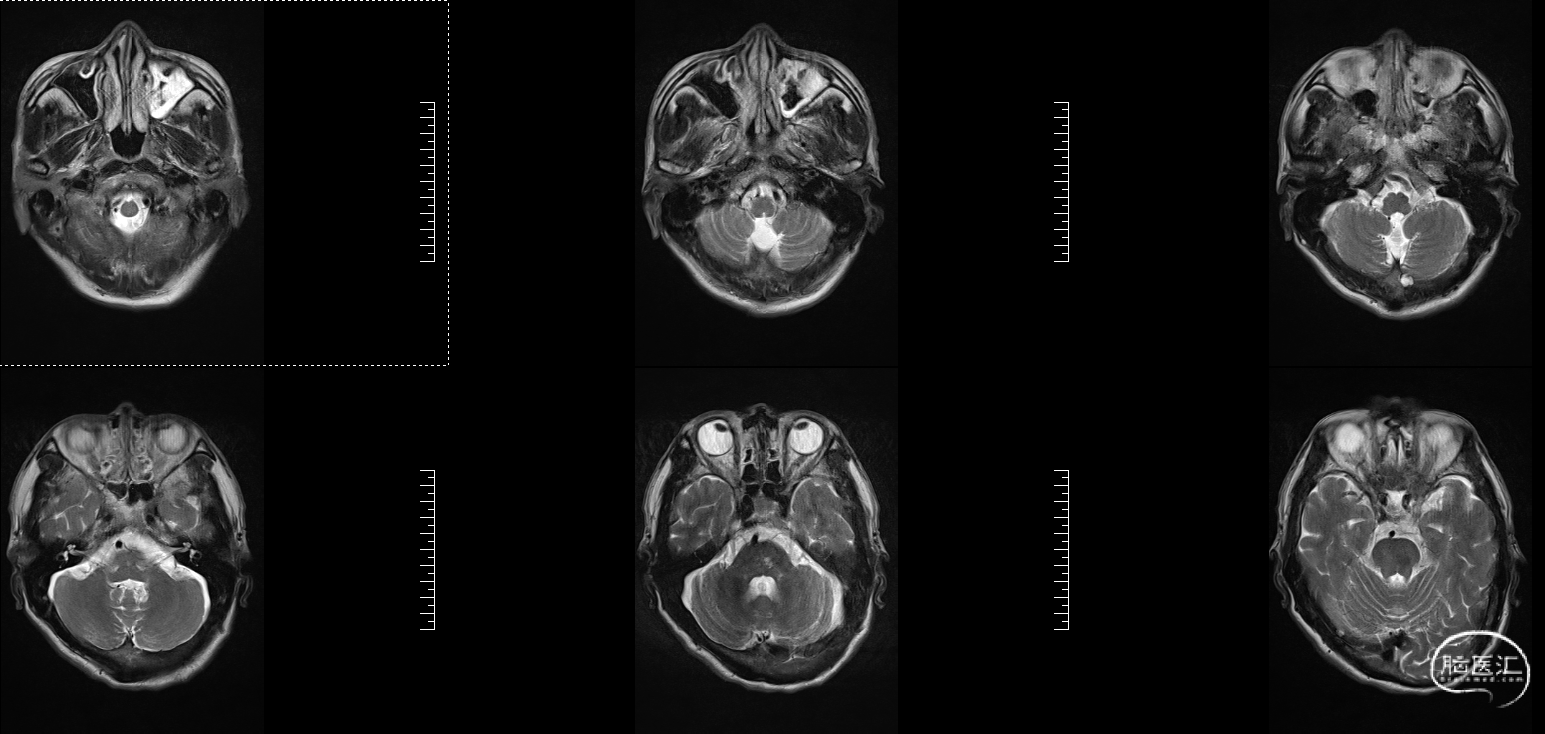

头颅MRI:左侧额顶叶急性脑梗塞;桥脑左份、双侧基底节、右侧脑室旁及双侧额叶多发腔隙性脑梗塞;双侧脑室旁及额顶叶轻度白质脱髓鞘;双侧上颌窦、筛窦、蝶窦炎;脑MRA示①右侧椎动脉纤细(变异)②左侧大脑后动脉P2段局部狭窄③左侧颈内动脉眼段局部严重狭窄④脑动脉轻度硬化改变,请结合临床及其他检查协诊。

溶栓同时急查头颅磁共振DWI。

溶栓同时急查头颅磁共振T2

2、MRI提示:左侧额顶叶急性脑梗塞。